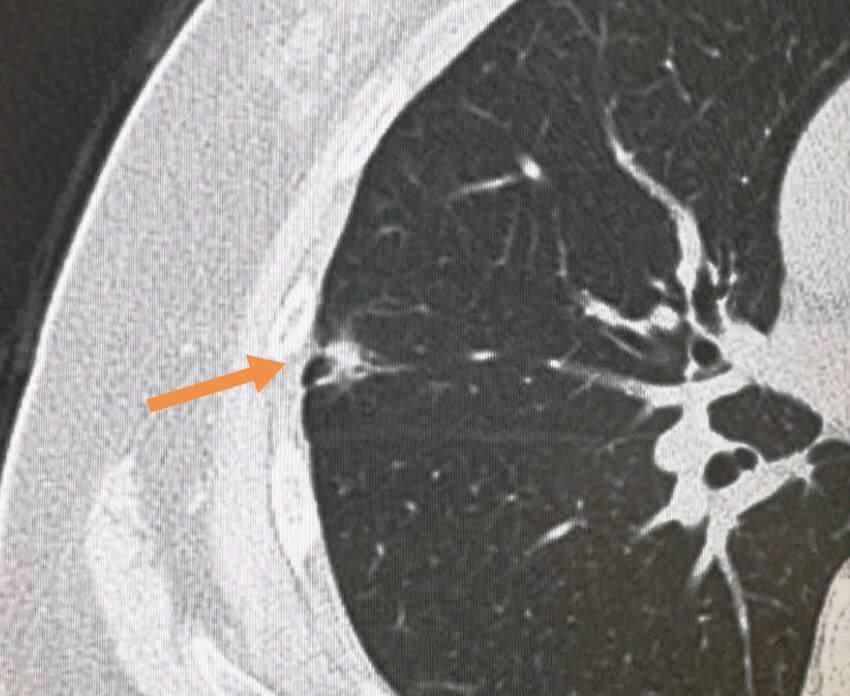

像这个磨玻璃病灶,长径4毫米,3年的时间长到下图这个大小:

手术切除证实为浸润性腺癌,没有耽误治疗。

这个结节属于生长比较快的。

一般来说,吸烟者或频繁接触二手烟者,发现肺结节要谨慎,随访间隔要缩短,因为这个群体的肺结节,可能生长速度更快一些。

上图是一位老年男子,抽烟半辈子,体检发现右下肺实性小结节,直径5毫米。

仅仅1年后,增大数倍并且广泛转移了,很可惜: